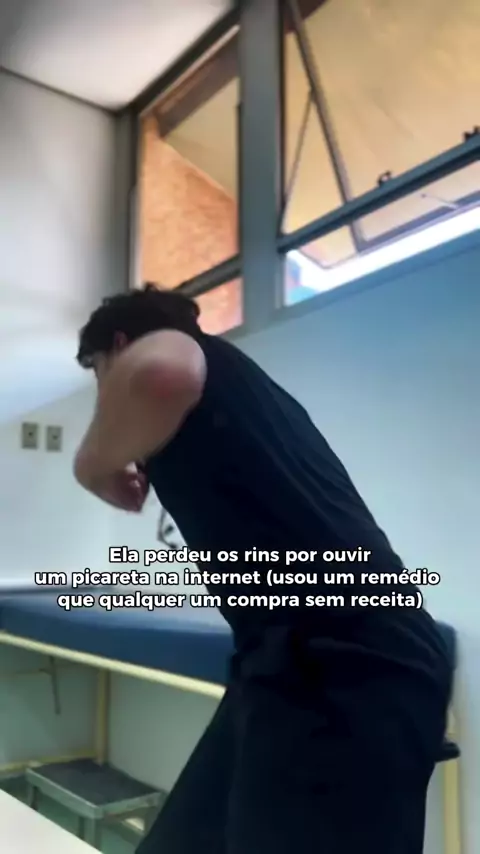

Na minha vez de ser médico galera? #medicina #saude #explorar #mbe #pbe